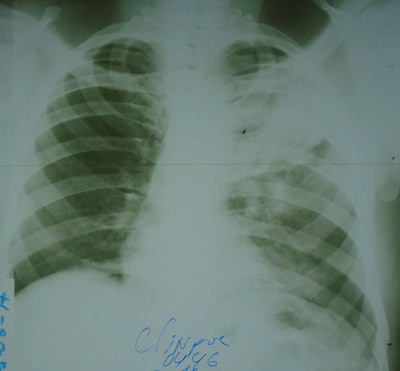

A sample input analyzed by the AI model. The film chest x-ray was photographed with a Sony Cyber-shot 20.1 MP digital camera.Mayo Clinical Proceedings: Digital Health

The group aimed to assess the diagnostic value of an AI model (qXR, Qure.ai) for TB using film x-rays photographed by mobile phones or digital cameras. The analysis used 498 images from patients seeking help for TB symptoms between January 2017 and March 2018 at health centers in Ethiopia and Guinea-Bissau who had a final diagnosis by clinical or laboratory tests.